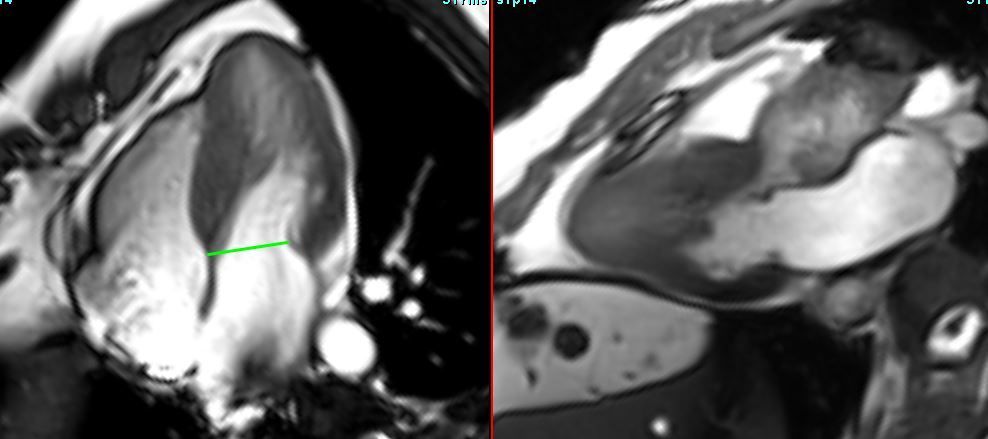

HCM with LVOT obstruction

COD 158 - Septum Predominant HCM and RVoTo

RVoTo involvement in HCM is uncommon but diagnosing it may change the management plan and prognosis